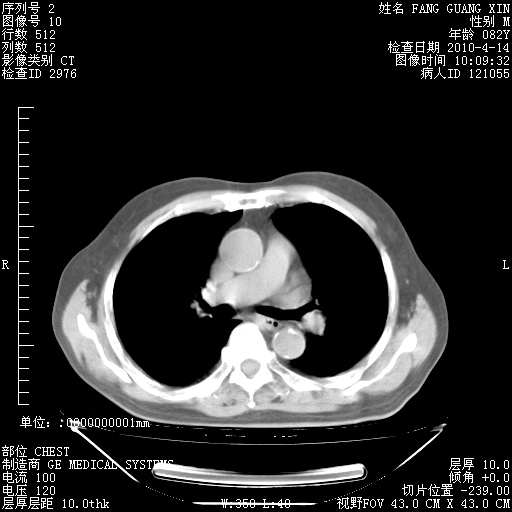

4月14日肺部CT